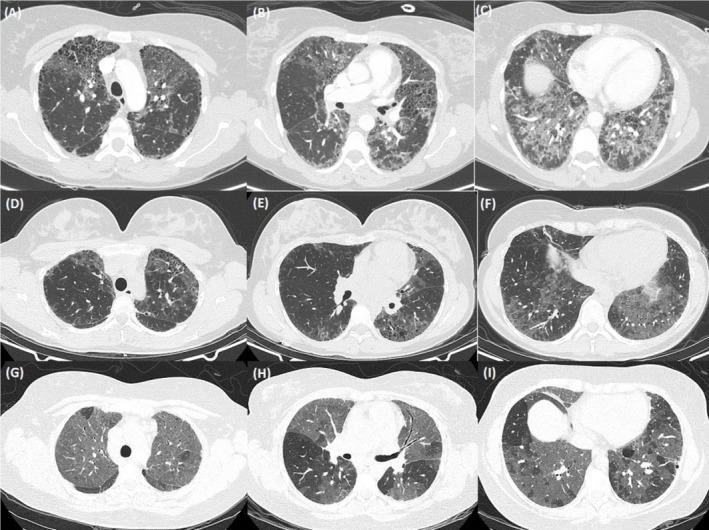

表面活性剂相关基因(SRG)变异是成人间质性肺疾病(ILD)的一种罕见但日益被认识的病因。由三磷酸腺苷(ATP)结合盒亚家族A成员3 (ABCA3)基因致病性变异引起的肺部疾病已在婴儿和儿童中广泛报道,但在成人人群中很少报道。由ABCA3变异引起的肺部疾病的罕见性和异质性在识别、诊断和管理方面提出了重大挑战。在本病例系列中,我们报告了三例继发于复合杂合ABCA3变异的独特的ILD成人病例,回顾了文献,概述了成人人群中这种疾病的情况,并强调了早期基因检测在出现不寻常ILD的年轻成年人中的作用。

Surfactant-related gene (SRG) variants are a rare but increasingly recognised cause of interstitial lung disease (ILD) in adults. Lung disease due to pathogenic variants in the adenosine triphosphate (ATP) binding cassette subfamily A member 3 (ABCA3) gene has been extensively described among infants and children but is rarely described in an adult population. The rarity and heterogeneity of lung disease due to ABCA3 variants raise significant challenges in recognition, diagnosis and management. In this case series we present three unique adult cases of ILD secondary to compound heterozygous ABCA3 variants, review the literature to provide an overview of this disease in an adult population and highlight the role for early genetic testing in young adults presenting with unusual ILD.